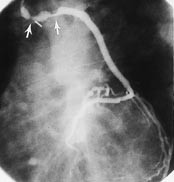

Ventrikulografien viste velfungerende venstre ventrikkel. Selektiv angiografi viste lukket ramus descendens anterior, sentral 90 %-stenose i ramus circumflexus og i høyre koronararterie. Kateterisering av et åpent venetransplantat viste at dette først gikk til en stor marginalgren fra ramus circumflexus, deretter videre til periferien av ramus decsendens anterior. Det var to sentrale 90 %-stenoser i venetransplantatet (fig 2) og en 75 %-stenose mellom transplantatet og ramus descendens anterior. Etter injeksjon i venegraftet fikk pasienten brystsmerter og uttalte senkninger i ST-segmentet i flere EKG-avledninger. Han ble behandlet med nitroglyserin sublingvalt og oksygen, med noe bedring.